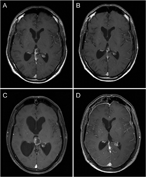

Intracranial monodermal teratoma presenting with growing teratoma syndrome

B. Khoo and others

Journal of Surgical Case Reports, Volume 2017, Issue 5, May 2017, rjx038, https://doi.org/10.1093/jscr/rjx038